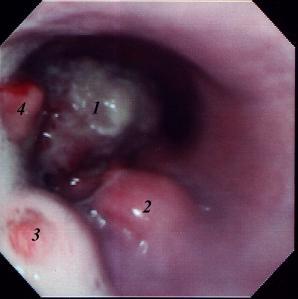

'n Definitiewe diagnose kan ook met endoskopie (Die sluk van 'n "kamera") gedoen word, maar die apparaat is baie duur en word net in groter veeartshospitale gebruik. (Sien Fig. 3) Die eiers van die wurms kan met 'n misondersoek gevind word, maar aangesien hulle heelwat kleiner is as die gewone wurmeiers, is dit nie altyd akkuraat nie. 'n Hond mag ook duisende migrerende larwes in die slagare hê sonder dat daar 'n enkele eier in die mis voorkom.

| Fig. 3: Vier granulome in die slukderm van 'n hond soos met 'n endoskoop gesien. |

Erkenning vir fig. 3: Dept. Kleindierchirurgie, Fakulteit Veeartsenykunde, Universiteit van Pretoria.